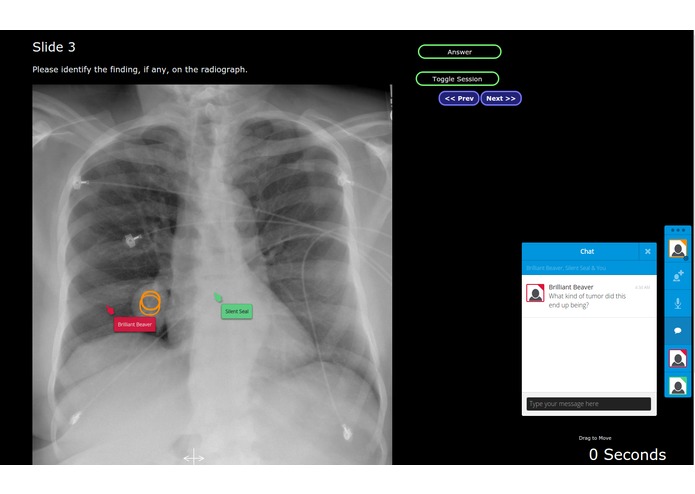

At scientific conferences the situation is worse - a lecture hall has hundreds of seats, so when the speaker asks the audience a question "do you guys see anything wrong with this X-ray? Where is the disease?" There is no participation - the speaker has a laser pointer, the audience has nothing.

The entire careers of radiologists and other imaging processionals rely on being able to communicate clearly using images. I created SharedDx to allow real-time collaborative discussion about medical imaging both in a real-life conference setting and in a virtual conference (e.g. conference call).

2. Everyone in the audience can jump into the presentation slide using their phone/tablets and point at abnormalities and pose questions to the speaker through a chat window.